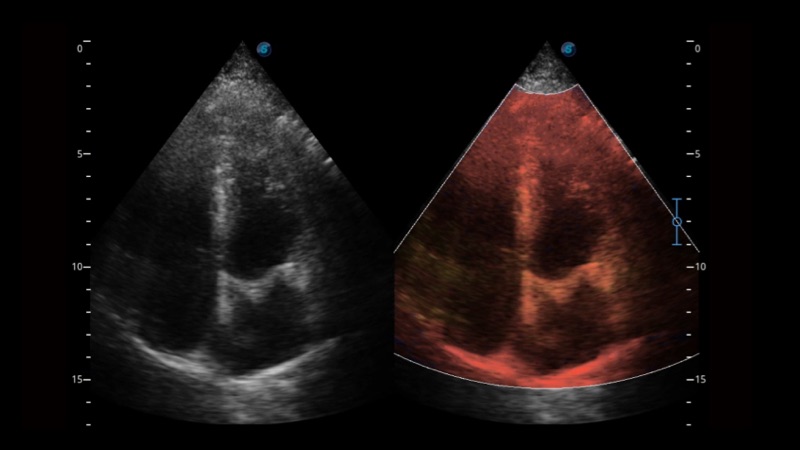

開立醫(yī)療通過不斷的技術(shù)創(chuàng)新,為大眾的生命健康提供持續(xù)關(guān)愛。P12 Plus采用全新一代超聲成像平臺,新平臺旨在將真實(shí)還原組織解剖結(jié)構(gòu)作為首要目標(biāo)。平臺采用全新集成化硬件模塊,搭載新一代芯片,系統(tǒng)性能得到大幅提升,為您的診斷提供了豐富的臨床信息。優(yōu)異的圖像表現(xiàn),豐富的探頭配置,全面的應(yīng)用功能,為您日常診斷提供了可靠的助手。

彩色多普勒超聲診斷系統(tǒng)